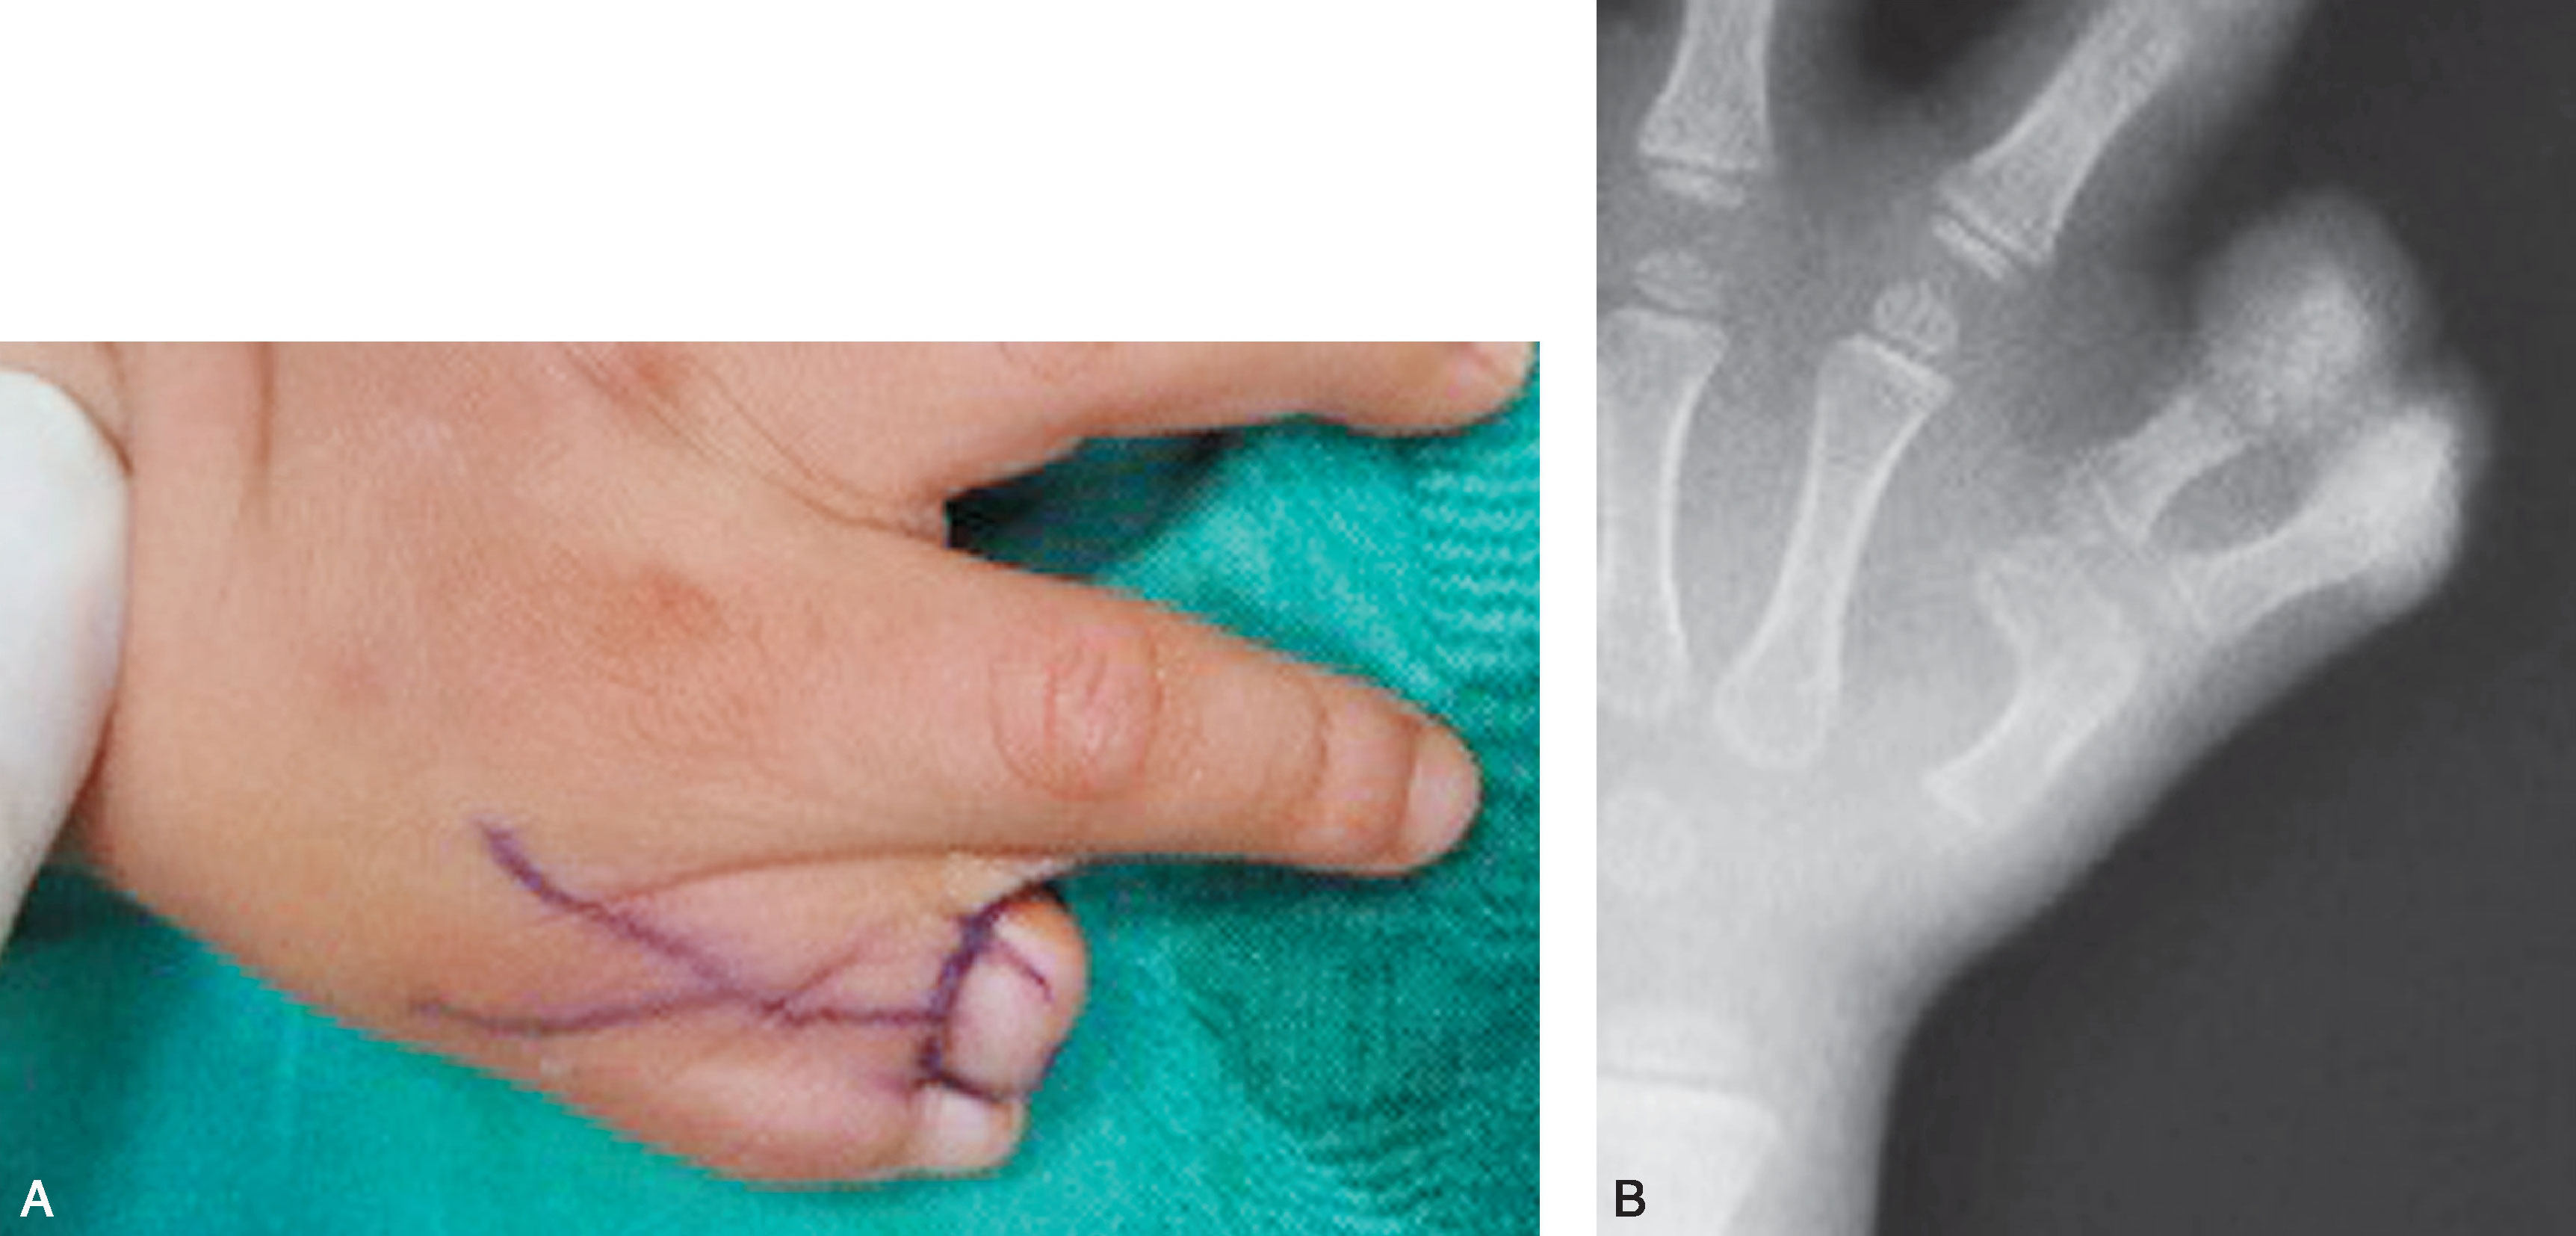

1.Ⅰ型 末节指骨未完全分裂,近节指骨正常或不正常,共用一个骨骺,并与近节指骨远端形成关节(图2-1-1~图2-1-4)。

图2-1-1 Ⅰ型病例1

A.主拇指与次拇指外形差异较大,各自有独立的指甲,远节尺偏(左侧);B.X 线片显示,虽然指骨远端分开,但基底共用一个骨骺,重建时需手术切除部分桡侧骨骺板,远节指骨尺偏需行近节指骨远端桡侧闭合楔形截骨,以纠正远节手指的尺偏畸形